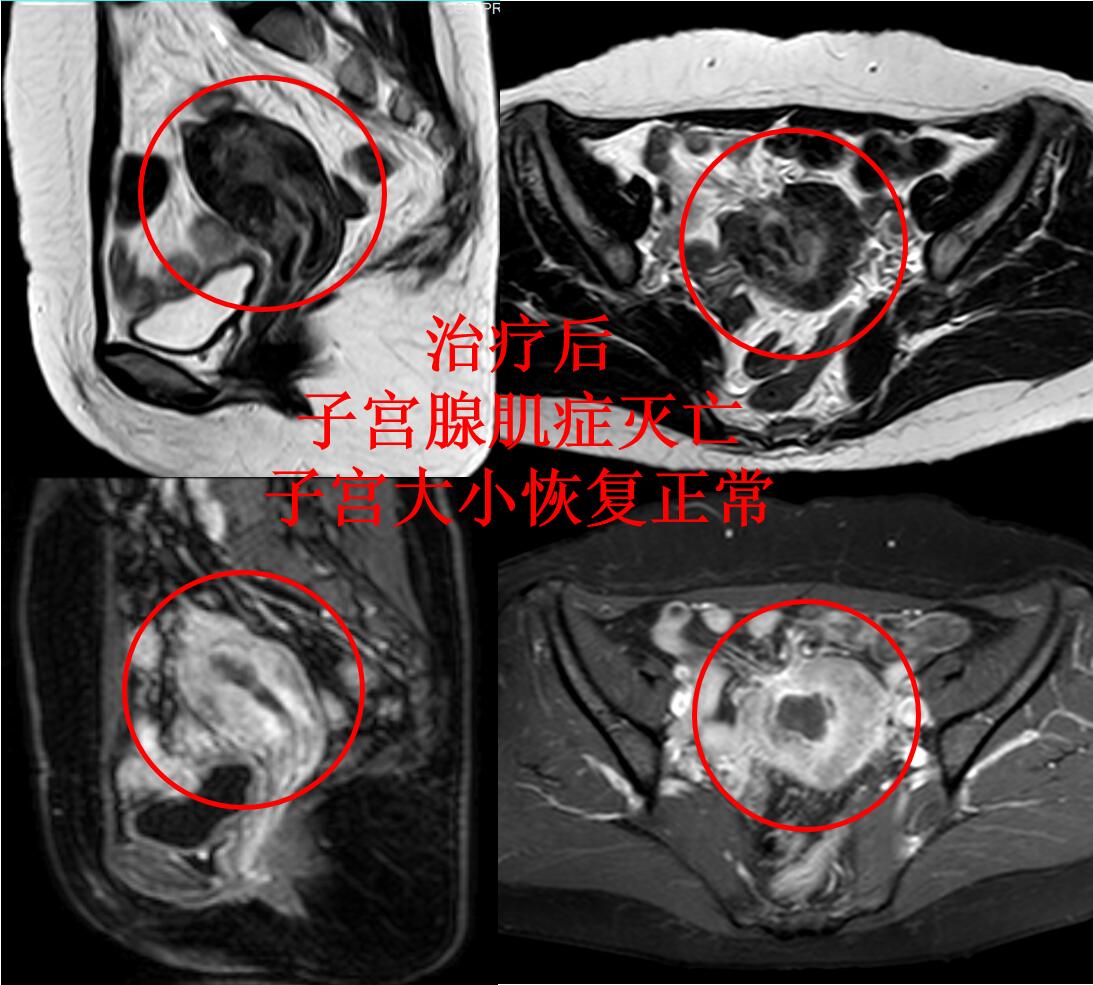

介入微创栓塞治疗后第2天,蓝护士即可下床步行活动。治疗后2个多月蓝护士来例假,无痛经,月经量明显减少,6天干净。3个月后复查磁共振显示:子宫腺肌症灭亡,子宫缩小(如下图)。